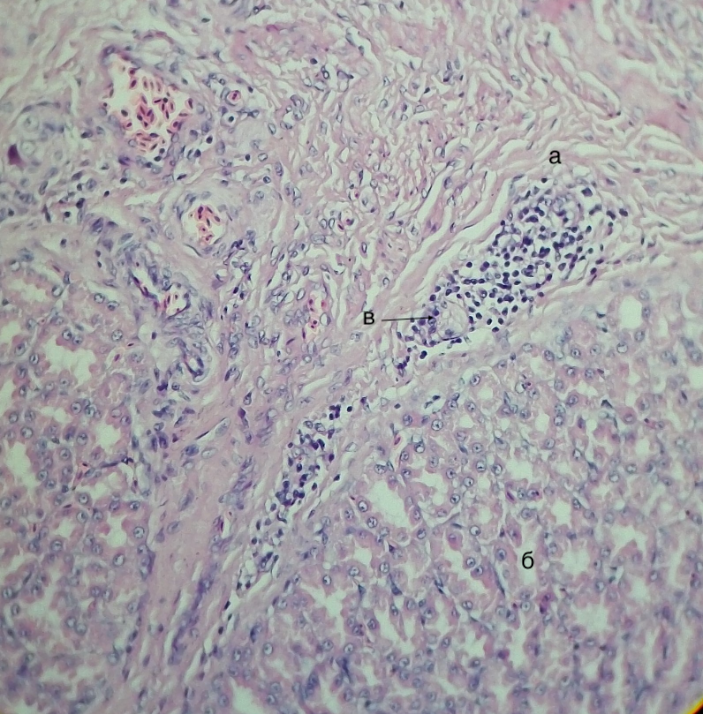

Рисунок 3 - Железистый отдел желудка утки кросса Агидель, подслизистая основа

а – лимфоидный узелок, б – плотные волокнистые структуры

Примечание: гематоксилин, эозин. Об. 10. Ок. 40